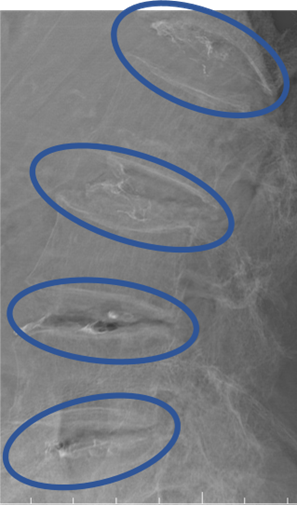

DiscoGelを入れた後の画像になります。

治療は 40分程度で終了

回復室で休憩後、歩いて帰院されました。